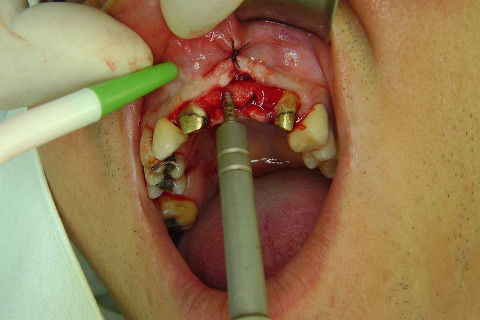

Cirurgia realizada hoje de manhã...No planejamento percebi medindo espessura do rebordo com especímetro que as medidas não estavam muito boas, ou o ideal, em torno de 4,5 a 5 mm ate´o terço médio do rebordo e melhorava no final, com 6 a 7 mm. Optei então por uma pequena expansão usando os expansores rosqueáveis. Aconteceu uma pequena fenestração na hora da fixação dos implantes, especialmente na região do 22 que fraturou o início da tábua óssea, mas não me preocupei porque não foi mais do que 2 mm de fratura em direção apical, o implante ficou infraósseo e com boa estabilidade (60 N no 21 e 40 N no 22). Esta fratura tb não deixou osso completamente solto, foi do tipo galho verde, deixei em posição e suturei normalmente. Só não fiz e nem estava planejado carga imediata mesmo, mais pelo motivo da oclusão inadequada do caso.

Fotos do caso